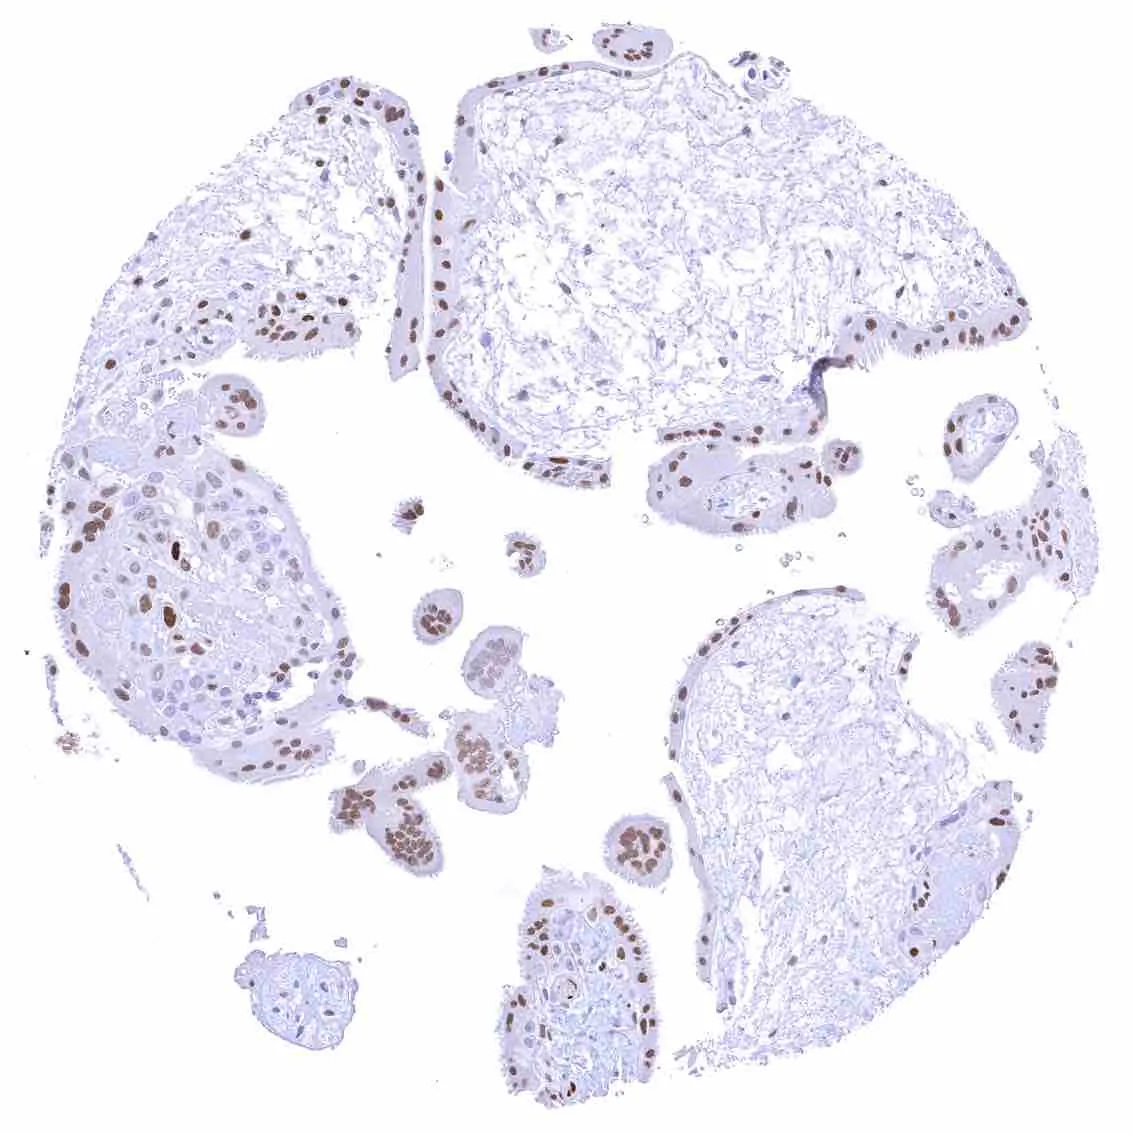

Placenta (amnion and chorion) – Moderate to strong nuclear p27 staining of most or all chorion cells. A weak to moderate nuclear p27 staining also occurs in a subset of amnion cells.